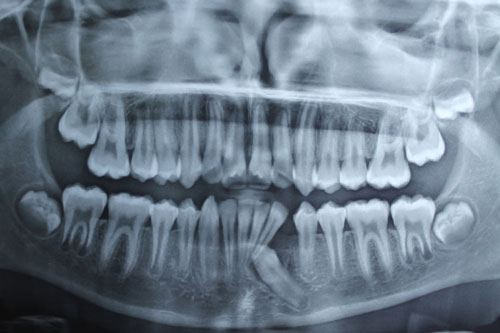

Removal of impacted canine